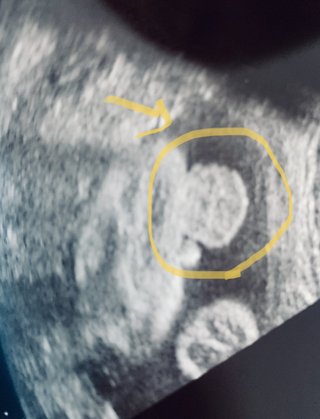

32w エコーで女の子→男の子 投稿画像

32w エコーで女の子→男の子